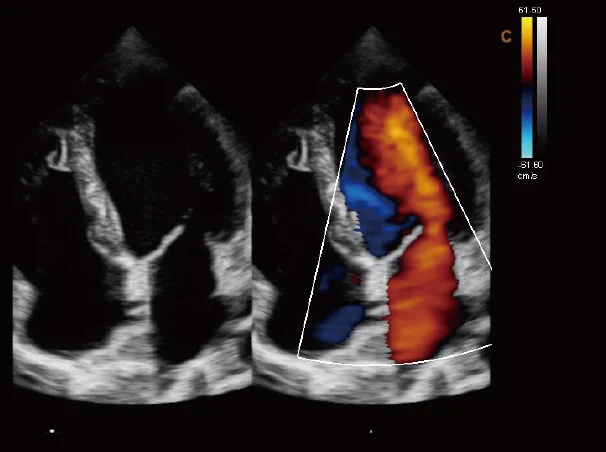

Ultrasound

Wide range of Ultrasound machines that suites a variety of applications from abdominal to rectal scans, we take in consideration how the world is moving towards mobility and mobile applications.

SonoScape Pro Pet E11

Smart Imaging

Introducing the first portable ultrasound with the C-Field+TM platform, redefining diagnostic imaging. Designed for veterinarians, it delivers unmatched clarity, ultra-fast processing, and seamless adaptability for all species. Experience Smart Imaging, Heartfelt Care—anywhere.

Equipped with cutting-edge veterinary software and optimized workflows, it embodies our commitment to Smart Imaging, Heartfelt Care – Wherever Their Journey Leads, with unparalleled performance and adaptability, this innovative system empowers veterinarians to provide exceptional care across all diagnostic applications,

Esaote MyLab Sigma; So Fast, So Easy

Esaote’s new MyLab™SigmaVET is the smart, portable solution that allows use of an ultrasound whenever a quick and complete diagnosis is required.